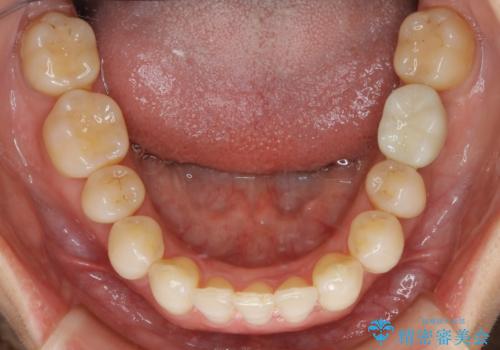

【抜歯】矯正治療とインプラントで正常な噛み合わせを実現

- 元々は矯正治療を主訴にご来院されました。

治療を始めるにあたり、精密検査を受けていただき全体の状況を把握したうえで矯正治療の計画を立てることとなりました。

その過程で左下の6番目の歯は治療が必要な状態であることが分かり、被せ物を外して内部を確認してみると根が破折してしまっていることが判明しました。

歯が深い位置で破折している場合は基本的には抜歯が選択されます。

様々な治療プランを患者さんと相談させて頂き、最終的にインプラントで噛み合わせを回復させていくこととなり、まず悪くなっている歯を抜歯することから開始しました。